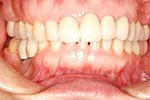

症例 15

① 治療前、左下奥歯がありません。

② インプラント手術後土台を立てたところです。

③ 固定式のセラミックの歯が入りました。

50才代 女性

総額:89万円(税別)

治療期間:4ヵ月

リスク副作用:噛み合わせに負担がかかりすぎるとセラミックが破損することがあります。